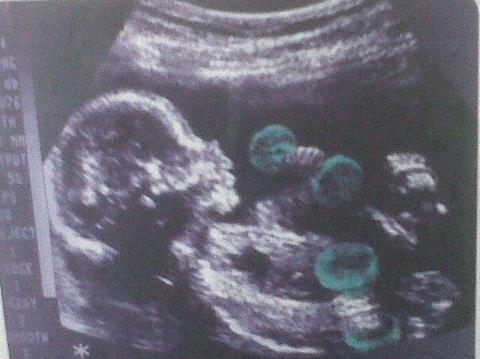

A köldökkukucskáló segítségével bármikor benézhetünk a pocaklakóhoz, s ezáltal közelebbi kapcsolatba kerülhetünk vele már a terhesség alatt is.

Nagy a boldogság Majkánál és Dundikánál: az egykori playmate közös gyermeküket hordja a szíve alatt, a hírek szerint a magzat már három hónapos.